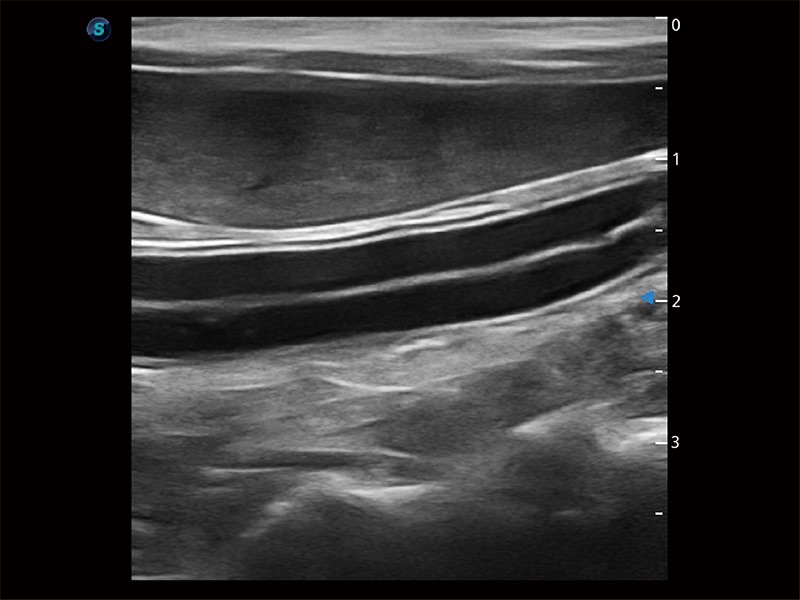

高性能和先进的临床应用工具可以为动物医生提供临床信心。ProPet 80 搭载了先进的腹部和浅表应用工具,帮助医生在日常临床实践中发挥前所未有的作用。

极大提升超低速微细血流的检出能力,同时更精准地滤除软组织和超声信号,为兽用医生提供以往无法通过常规血流获得的疾病诊断信息。

为精细结构及组织边缘提供高清晰度的图像和更大的成像视野。帮助减轻医生的用眼疲劳,快速精准获得测量的数据。